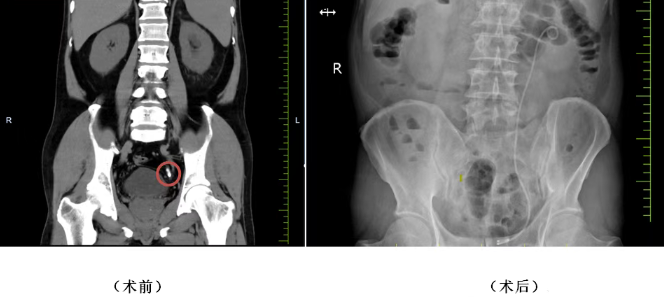

患者李女士(化名)因左侧腰腹部间断疼痛1年入院,检查发现左侧输尿管腹段结石伴左肾积水,同时合并2型糖尿病,病情相对复杂。张宝主任团队先为其实施左肾造瘘术,快速缓解尿路梗阻、控制感染,为后续手术创造安全条件。待患者身体条件稳定后,团队通过经尿道左侧输尿管镜钬激光碎石取石术,在高清内镜下精准定位结石,利用钬激光高效击碎并取出结石,同时置入输尿管支架保障术后引流。术后患者排尿通畅,无发热、腰痛等不适,顺利康复出院。